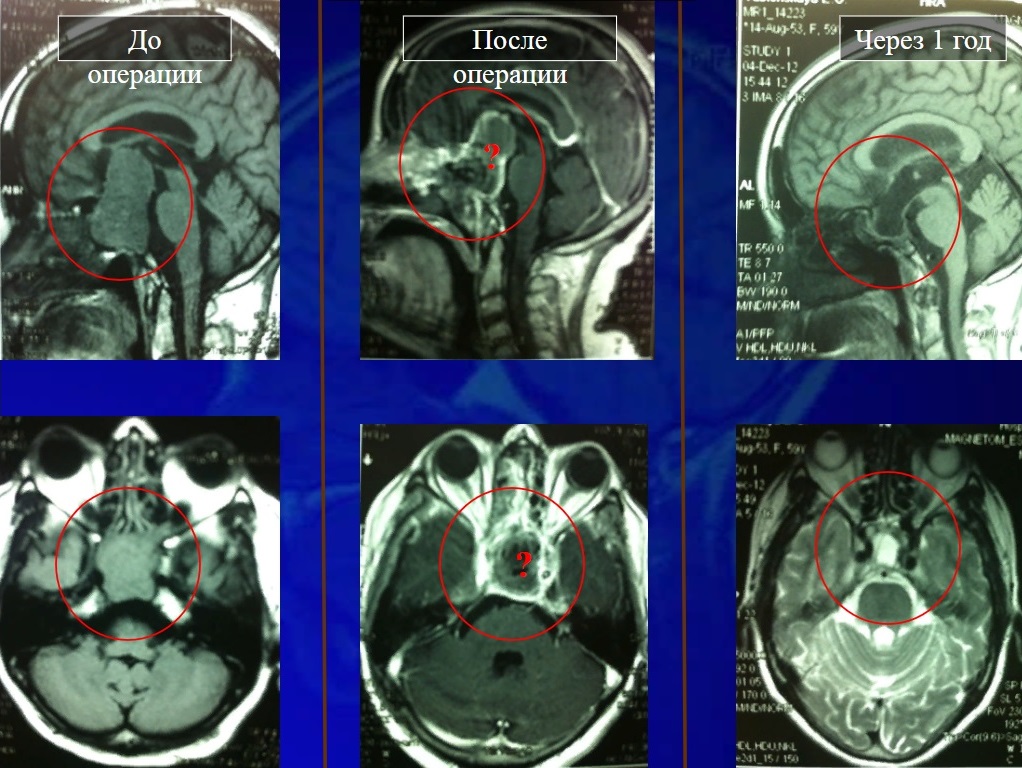

Микроаденома форум 110 фото